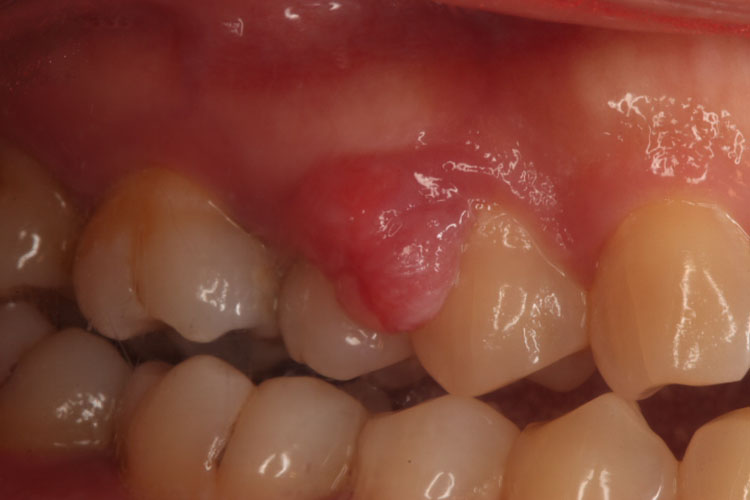

牙龈瘤是一种瘤样增生物,临床主要表现为牙龈乳头处的肿块,多呈圆球形或椭圆形。

好发于牙龈乳头,肿块多呈圆球形或椭圆形,有时呈分叶状,直径由几毫米至1~2cm,带蒂者如息肉状,无蒂者基底较广。血管性和肉芽肿性牙龈瘤质软、色红,纤维性牙龈瘤质地硬而韧,色粉红。一般无痛,牙龈瘤生长较慢,较大肿块可被咬破而伴发溃疡、出血或感染,此时自觉有疼痛。